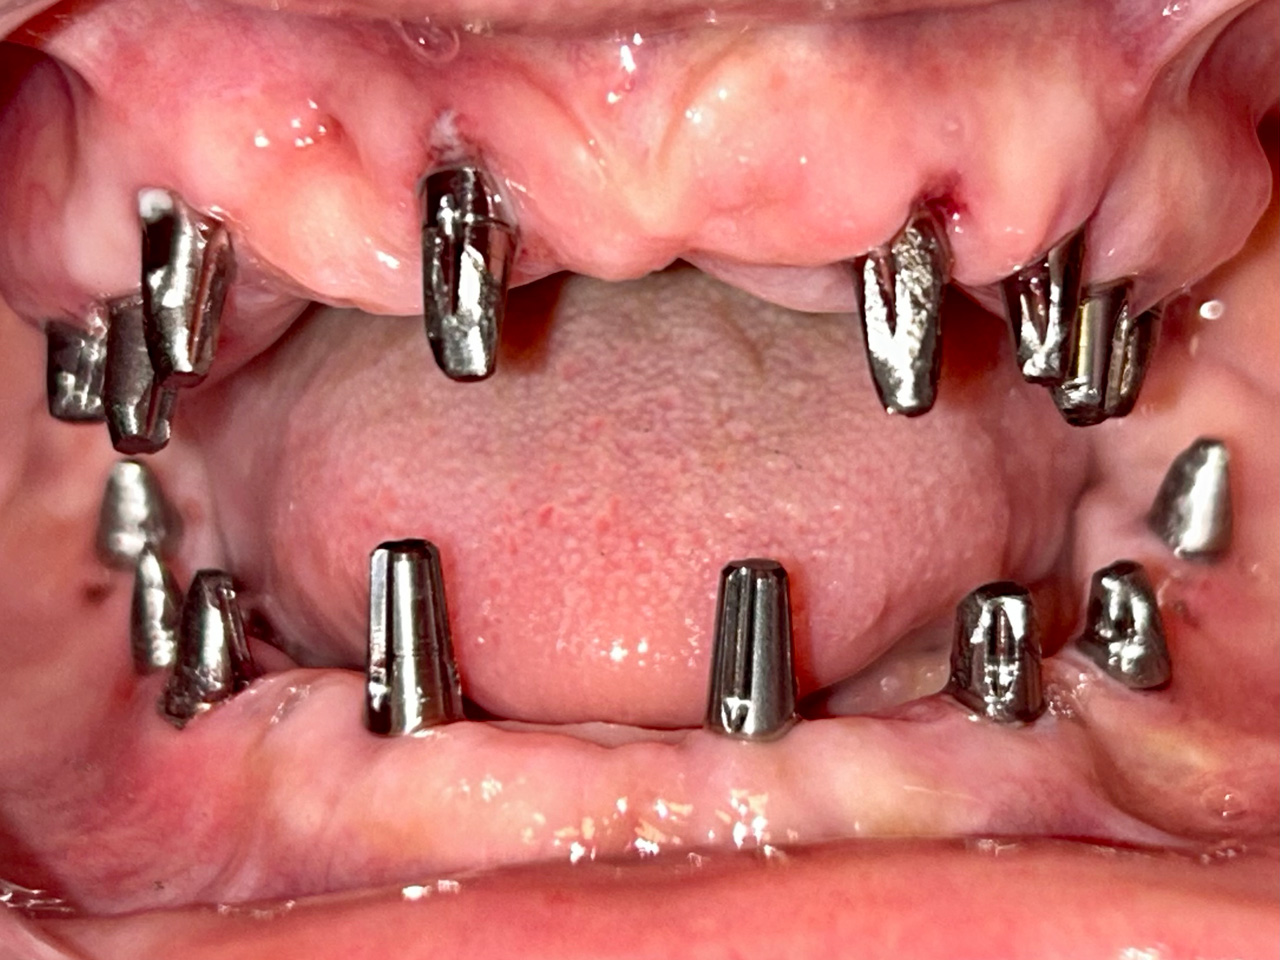

Teljes fogatlanság helyreállítása 2 nap alatt

Teljes fogatlanság helyreállítása 2 nap alatt azonnal terhelhető svájci IHDE implantátumokkal és PMMA műanyag hidakkal. Intraorális szkennerrel vettünk lenyomatot az implantáció után, és erre a digitális mintára készítette el a fogtechnika a hidak digitális tervezését, majd faragta ki műanyagból. Ezt a gyors munkát az azonnal terhelhető implantátumok és a digitális lenyomat, tervezés segítségével tudtuk megcsinálni mindössze 2 nap alatt. Dr. Kelemen Péter és a Symbion Fogtechnika munkája.